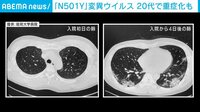

東京都内では新規感染者のうち、基礎疾患のない若年層も重症化するケースがあるとされる“イギリス型”(N501Y変異ウイルス)と呼ばれる変異ウイルスの割合が急増している。

「この“N501Y変異ウイルス”というのは、501番目のタンパク質のアミノ酸がNからYに変わったウイルスという意味で、正式にはB117と呼ばれている。ウイルスに変異があるかどうかPCR検査で調べていたイギリスで最初期に見つかり、あれよあれよという間に国内で変異していったため、イギリス株とも呼ばれている。これは重症化率が約1.6倍という研究結果が出ている。